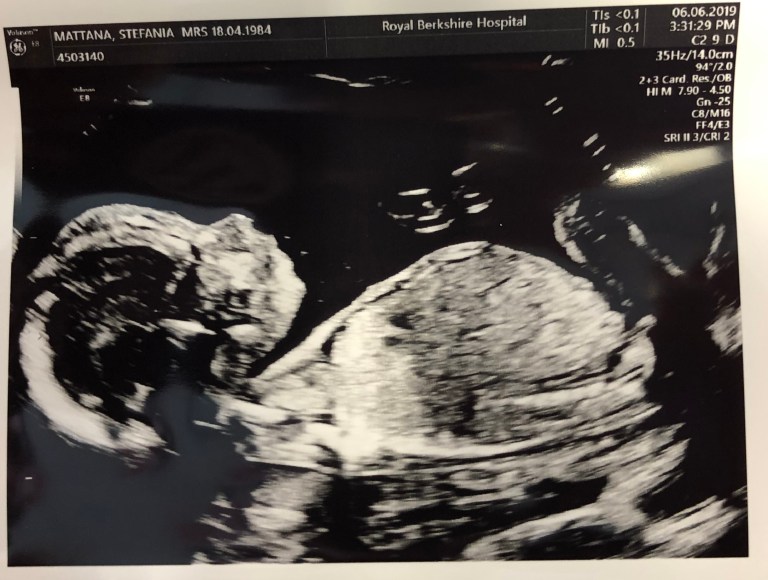

It’s scan day, just 24 hours before the official due date. The scan shows that Frosty has gained other 300g, the same weight I gained on the same span of time. This means once again that Frosty is taking the best nutrients out of me while I’m not gaining any unwanted fat.

The ObGyn happily confirms that Frosty’s head is nicely engaged, and it’s sort of “working” on softening the cervix.

OMG it’s due date! After 40 weeks, Frosty today weighs around 3kg (6.6lbs). It seems like yesterday when Frosty was that tiny little 5-day frozen embryo adventuring in my uterus.